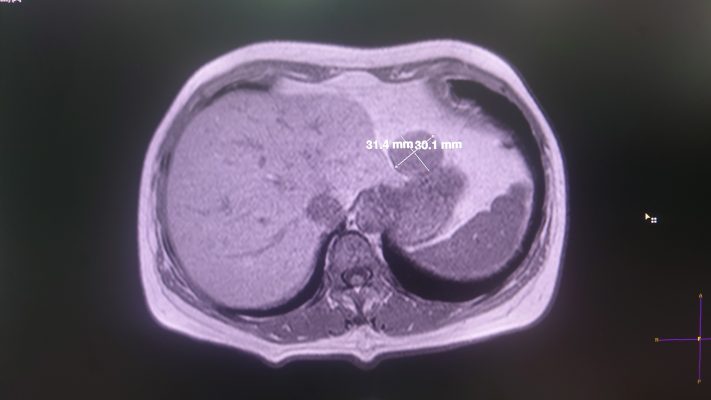

+ MRI ổ bụng: Khối tổn thương có tín hiệu đồng nhất trên các chuỗi xung, liên tục với thành dạ dày bờ cong nhỏ, có xâm lấn lớp cơ, đẩy lớp thanh mạc, lồi hẳn ra ngoài dạ dày, kích thước 25 x 25 x 35 mm, bờ đều, giới hạn rõ. Kết luận theo dõi U mô đệm dạ dày.